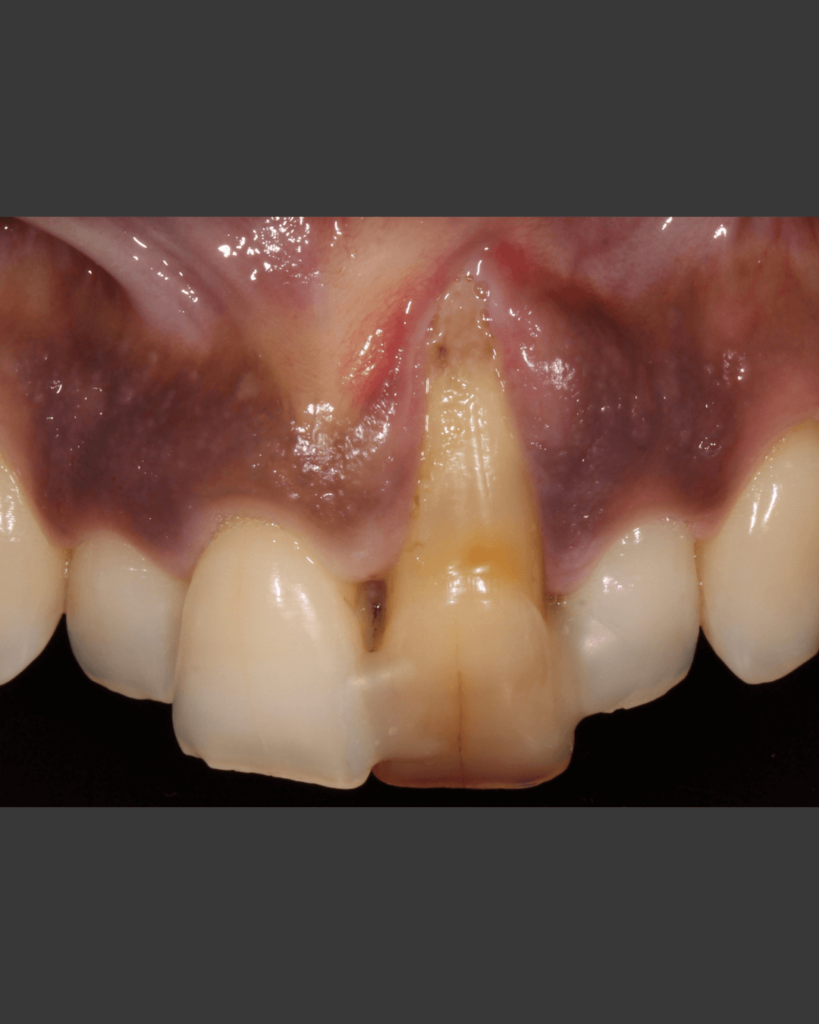

Klinischer Fall

NeoGen® Cape PTFE-Membran, fixiert auf einem gleichzeitig eingesetzten Implantat.

Nach 3 Jahren Entwicklungszeit stellen wir Ihnen die neu entwickelte NeoGen Cape PTFE-Membran vor. Besonders in Fällen von bukkalem Knochendefizit in der ästhetischen Zone ist diese innovative Fixierungsmethode eine hervorragende Lösung für die Behandlung solcher Fälle.